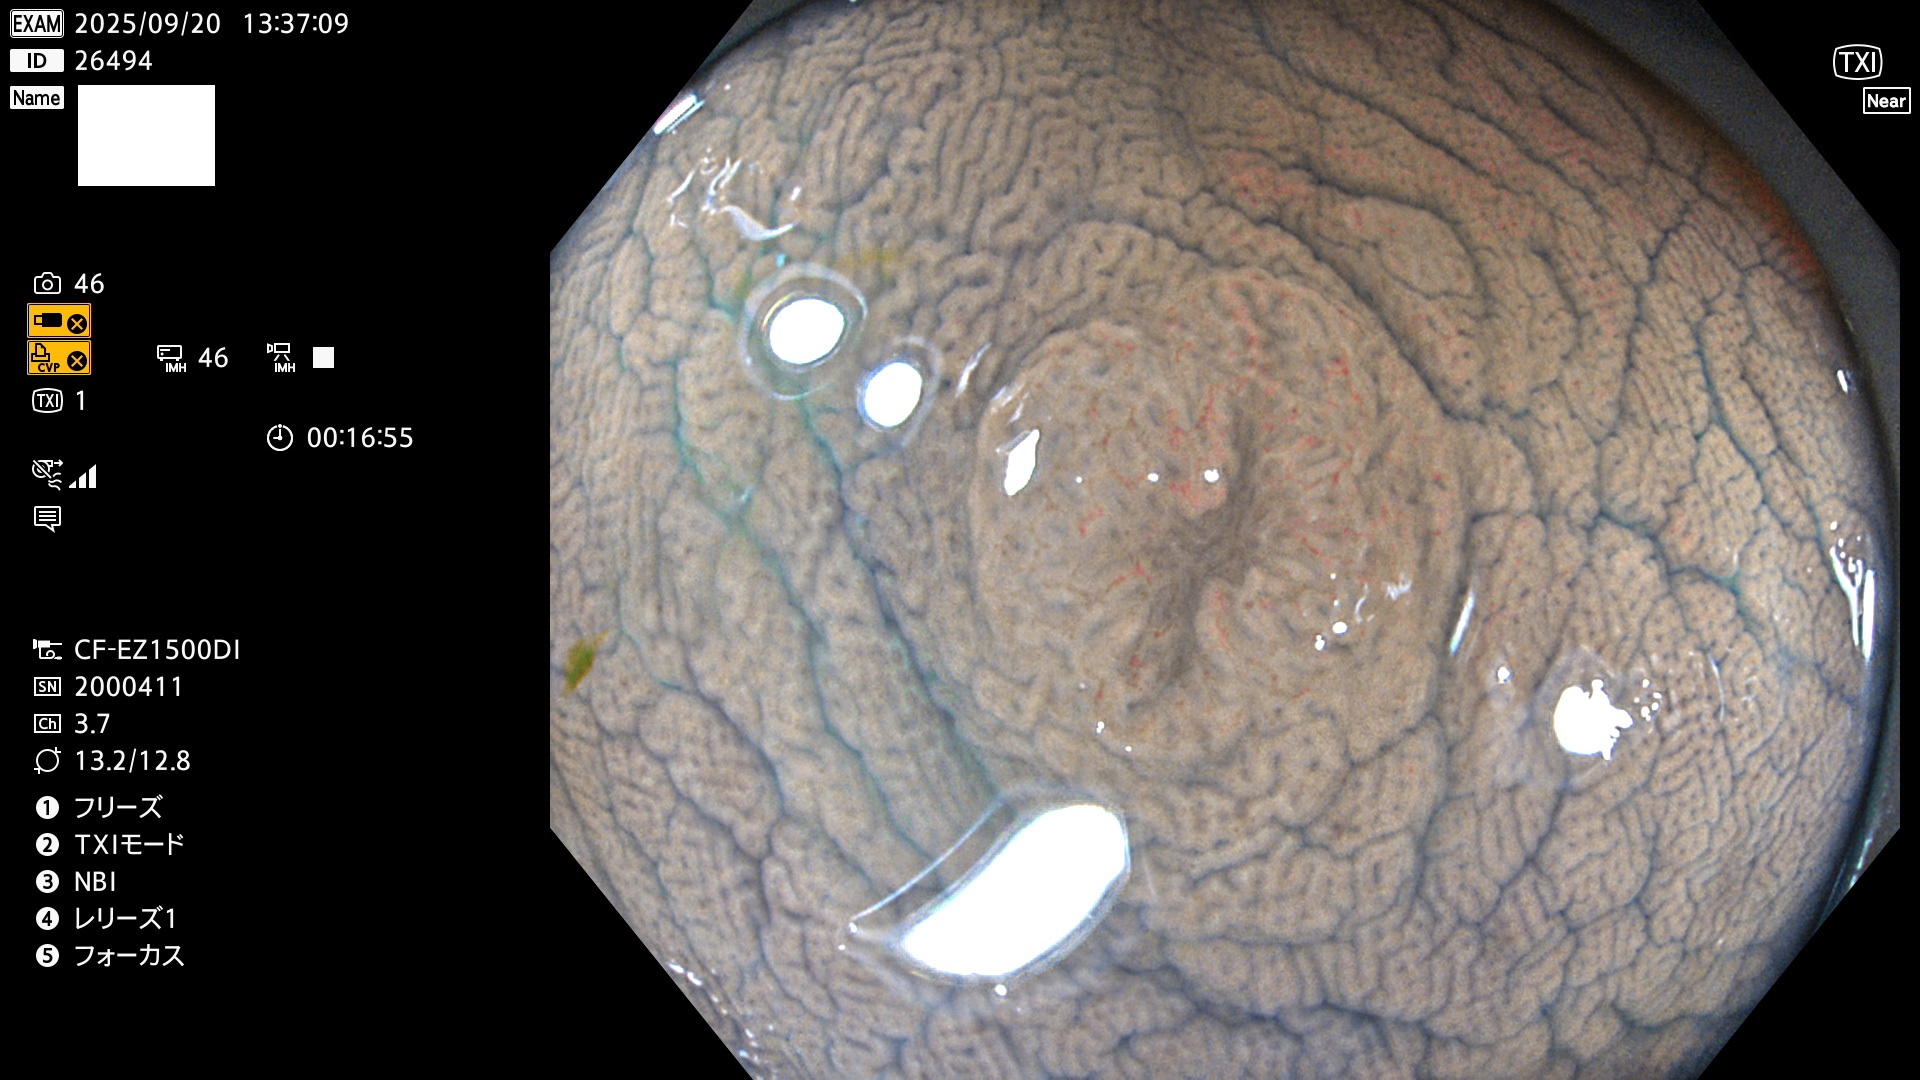

完全に平坦な物をUb、陥凹している物をUcと呼びます。Ubは認識が困難で、Ucはびらん(炎症)と紛らわしいために見落とされやすく、「内視鏡後・大腸癌」の原因になります。

専門的)何故、陥凹していると危険? 癌遺伝子の変異が蓄積すると細胞分裂が盛んになり隆起するのでは?と通常は思われるでしょう。しかし実際は逆です。これは2022年の記事にある「細胞はストレスに直面したら細胞分裂を止める(Dormancy 細胞老化に入り休眠する)という生命の基本的現象」によるものです(Oncogene Stress)。細胞老化を起こすのが癌抑制遺伝子で、この安全装置(ブレーキ)が壊れると癌になります(休眠からの覚醒)。ですから陥凹は「まだ癌では無いが癌化の直前」を意味します。特に「小サイズなのに陥凹している」病変は短期間に腫瘍進化(IntraTumor Heterogenity⇒2021年記事)が起きたことを意味します(=ゲノム不安定性)。

専門的)Uc=De Novo癌? 内視鏡の解像度が低かった時代、このような説もありました。しかし今日の高精度内視鏡では良性の微小なUc型腺腫(APC遺伝子異常の腺腫)が日常的に見つかります。Ucこそが多段階発癌(Adenoma-Carcinoma Sequence)のMain Routeです。

毎週の検査(木・金・土・日)に発見されたUbとUc型・腺腫を、その週の日曜の夜にUPし1週間、提示します。

2025年9月17日〜9月21日の4日間(40件)6個 (Uc_ADR=6個/40人=15%)